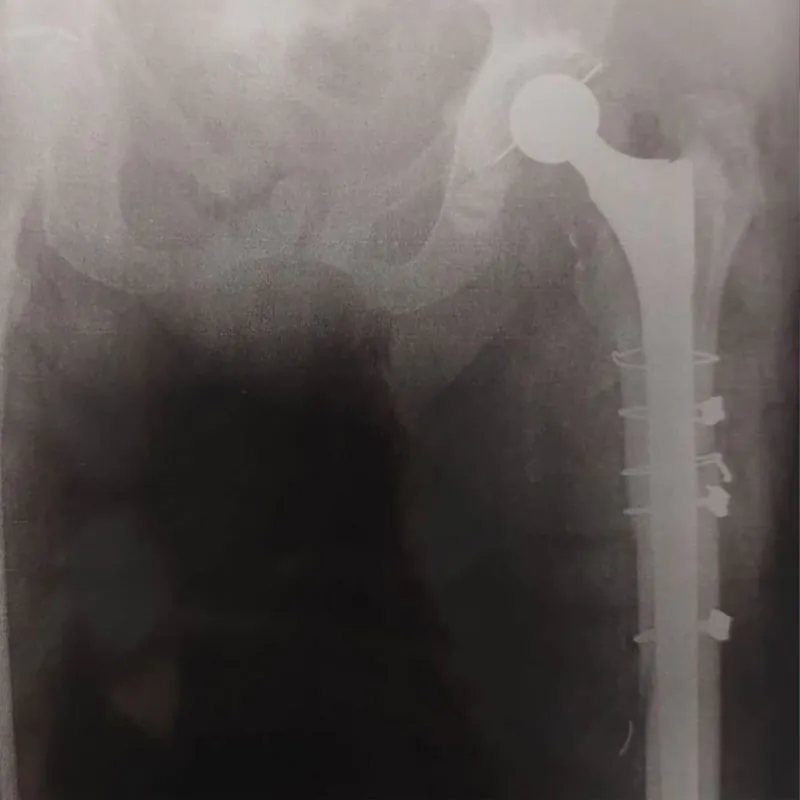

Fraturas complexas exigem uma abordagem especializada para garantir a correta alinhamento e cura dos ossos.

Nossa expertise em ortopedia nos permite tratar fraturas de membros superiores, inferiores, pelve e acetábulo com precisão e cuidado, promovendo uma recuperação eficaz e segura.